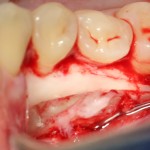

Костная «дверца» на время отделяется и убирается в физраствор, а мы видим следующее:

Это фолликулы и, частично, коронковые части сверхкомплектных зубов.

Теперь аккуратно нам нужно выделить сами зубы:

А вот они! Далее мы руководствуемся главным правилом хирурга-стоматолога: